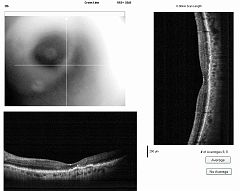

REPERTOIRES ANGIOGRAPHIES

Chaque dossier correspond à un cas dans lequel peuvent se trouver plusieurs examens à des dates différentes.

Path: /3101-20100827-01/03-08-2011/thumbs